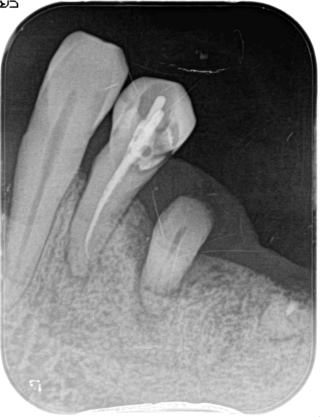

歯内療法:根管の湾曲:神経はまっすぐとは限らない